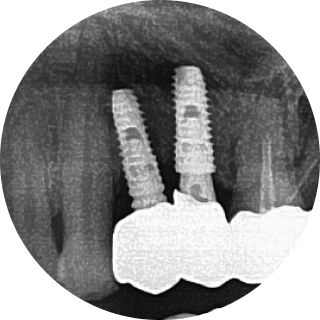

많은 치과의사들이 보철 중심으로 계획된 임플란트 시술의 중요성을 인정합니다.

그리고 이 과정에서 디지털 치과로의 전환이 필요함을 인정합니다.

그러나 비용적인 문제, 새로운 장비 기술 도입의 두려움, 필요성을 못 느끼는 등의 이유로

디지털 진료 방식을 도입하지 못하고 있는 치과가 많습니다.

이제는 임플란트 회사, 임플란트 브랜드 선택의 관점에서 벗어나서 임플란트 수술 진단부터 최종 치아 제작까지. 이 모든 과정에서 보철학적 목표를 디지털 방식으로 어떻게 완성해 내는지가 선택의 관점이 되어야 합니다.

이로운 치과는 간단하고 정확하며 안전한 치료를 위한 디지털 진료 방식을 지향합니다.

잘 못 심은 임플란트의 예시입니다.

이로운 치과는 디지털 진료를 통해 정확한 임플란트 식립 위치를 파악하여

아날로그 치료에서 발생할 수 있는 문제를 예방합니다.

개인 맟춤 디지털 수술 가이드

덴티움 임플란트

환자 맞춤형 지대주

CAD/CAM 지르코니아 크라운

이 모든 술식, 장비, 소프트웨어 노하우가 집약된

이로운치과의 디지털 임플란트